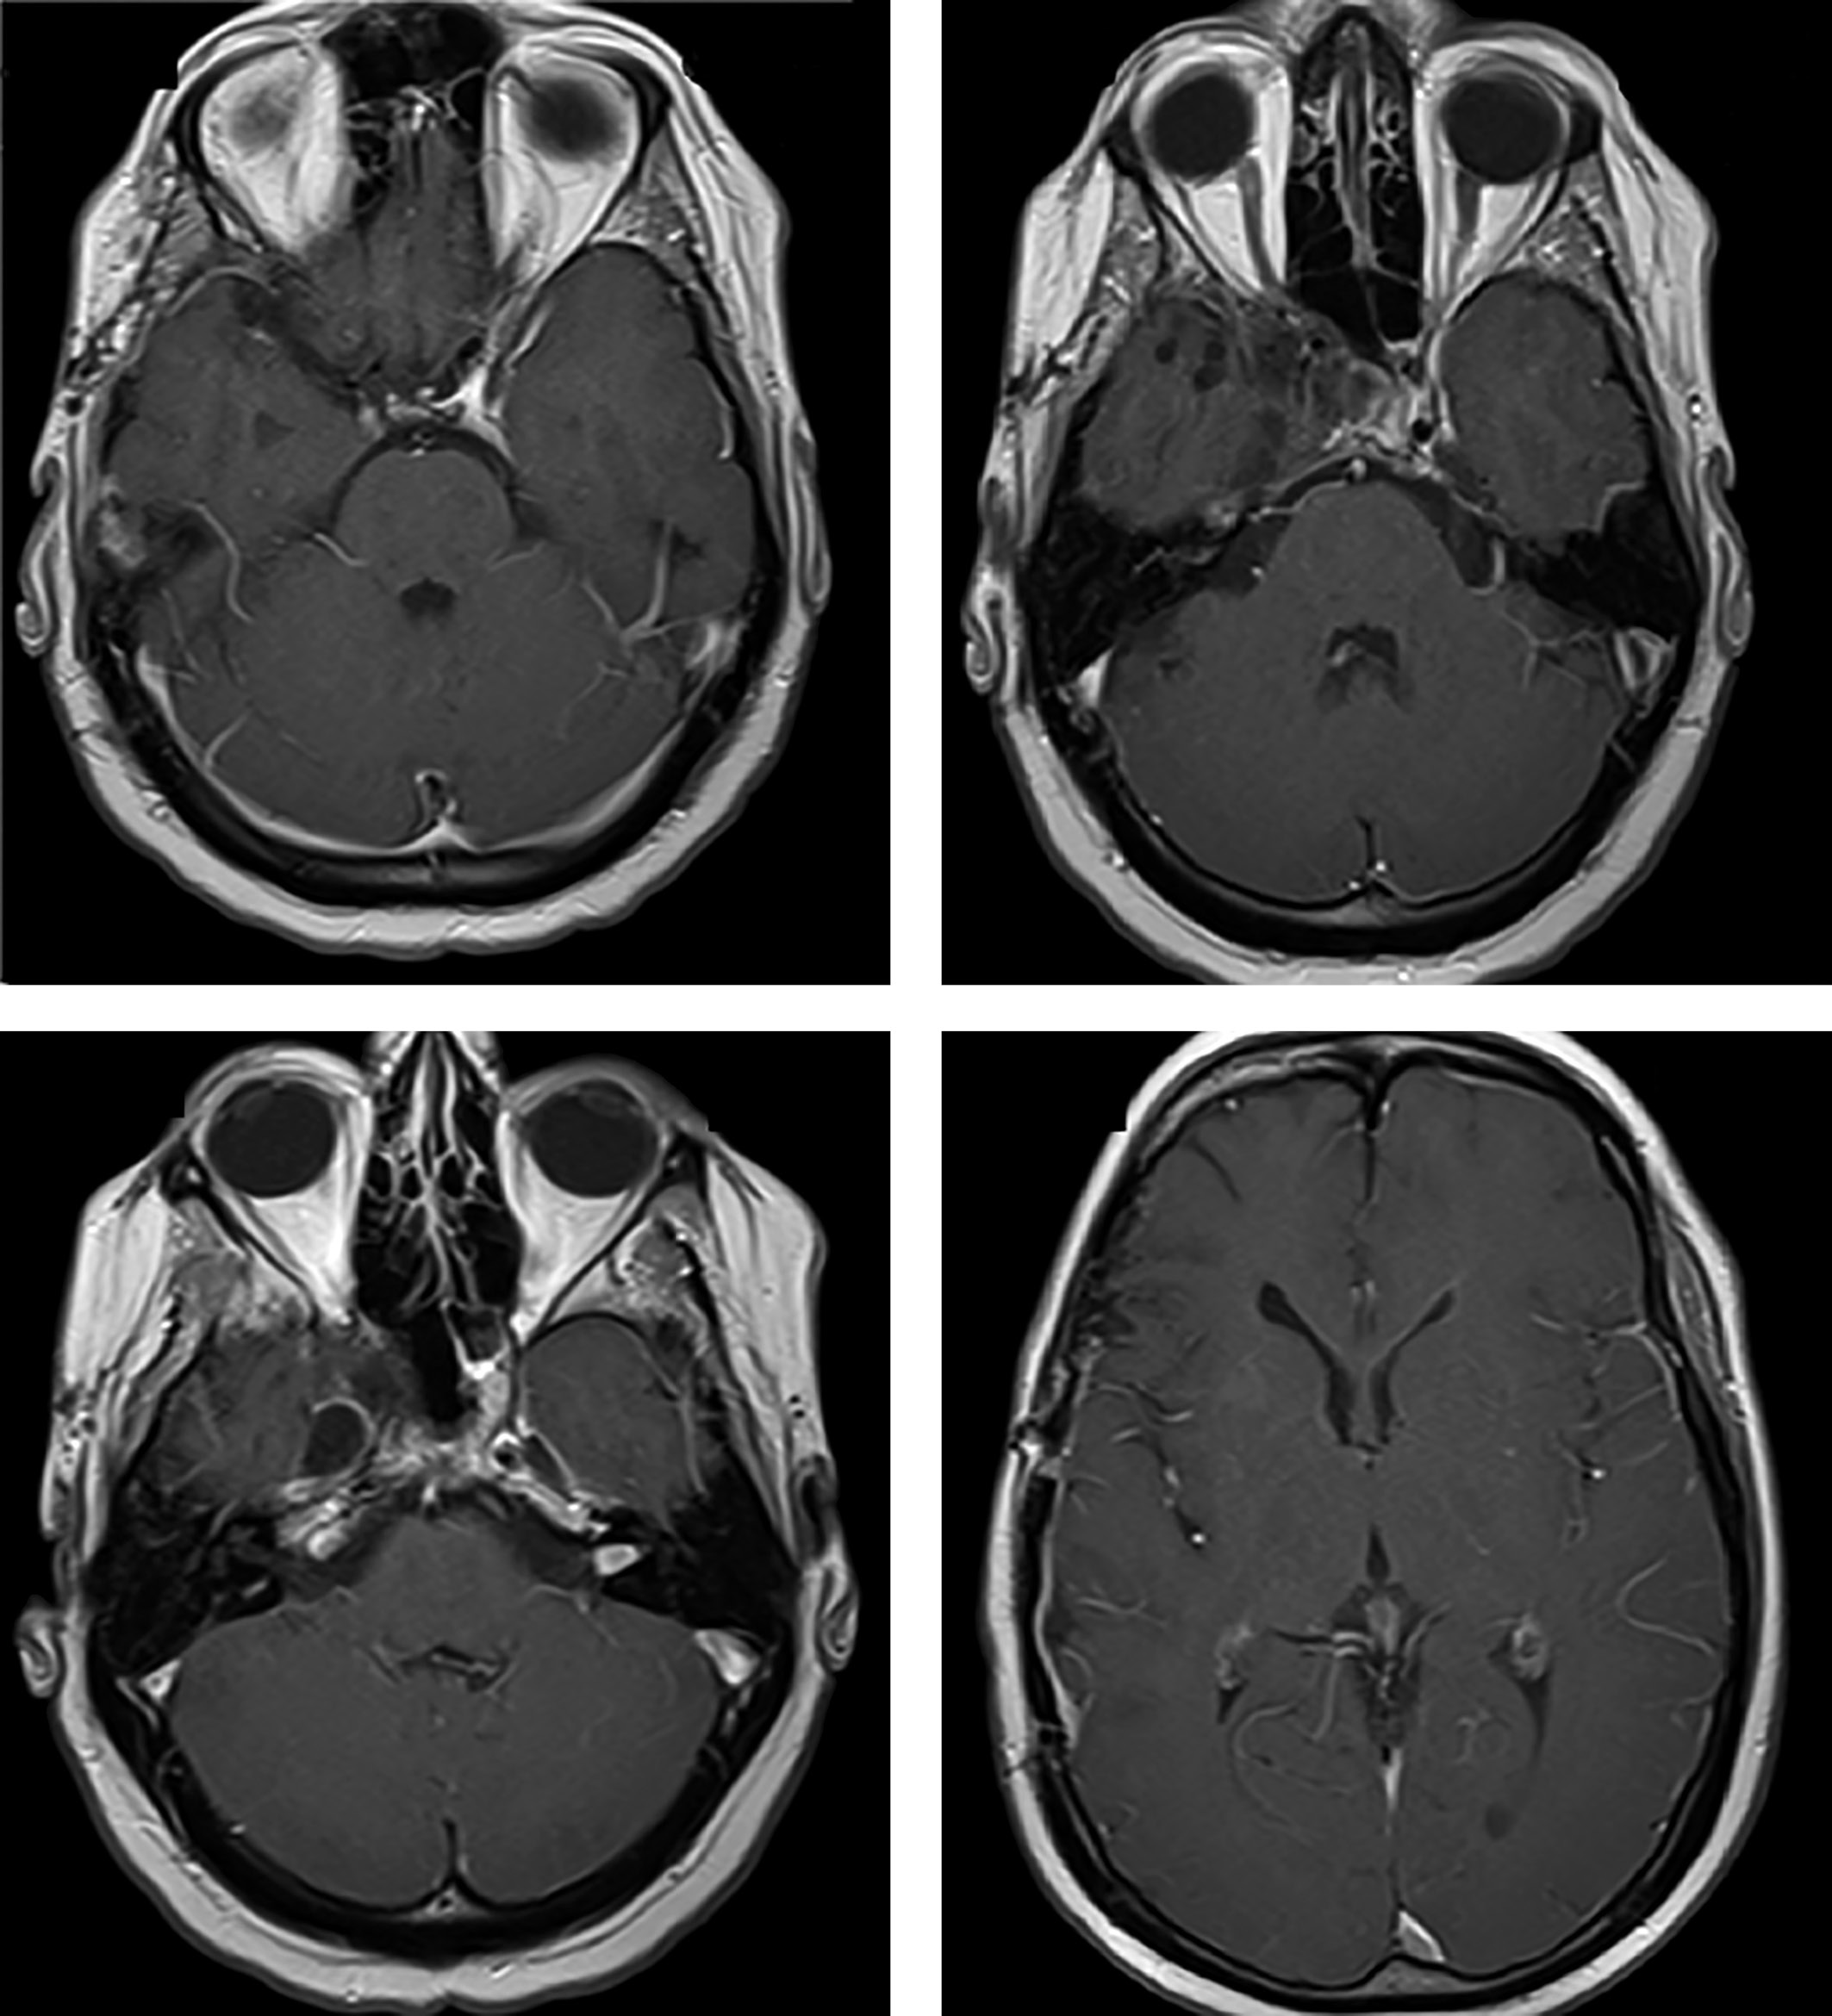

С декабря 2017 г. к таблетированной терапии гидрокортизоном и левотироксином добавлен трансдермальный гель тестостерона. При ежегодных контрольных осмотрах с 2018-го по 2023 гг. рецидива опухоли не выявлено (рис. 4). На фоне приема каберголина 2 мг в неделю сохраняется нормопролактинемия (ПРЛ — 149 мЕд/л). Состояние пациента удовлетворительное, он самостоятельно себя обслуживает и ведет обычный образ жизни.

Рисунок 4. МРТ (2020–2023 гг.) — не отмечено продолженного роста опухоли.